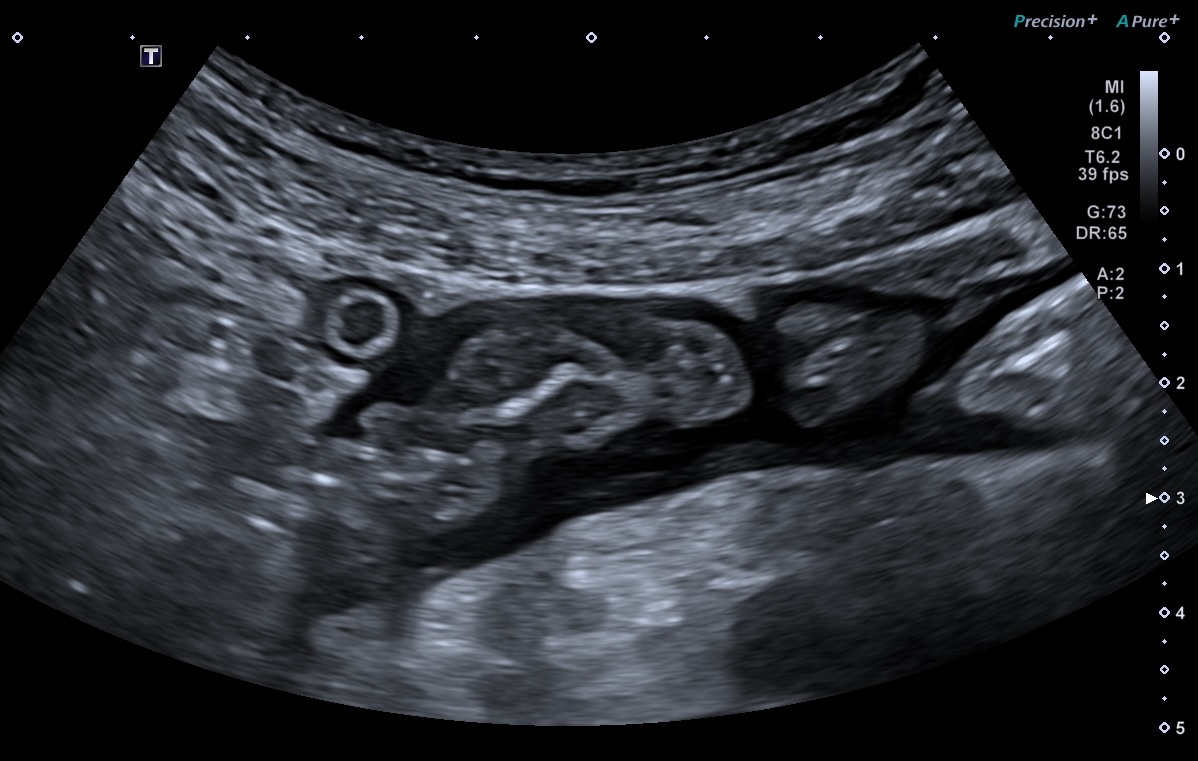

L'épaississement se mesure entre la muqueuse (hypoéchogène) et la musculeuse (hypoéchogène),

Ci dessous même portion avec et sans compression douce.

Il faut faire la moyenne de plusieurs mesures (≥3) en coupe longitudinale et transversale

L'échographie est la technique radiologique qui a la meilleure résolution (millimètre)